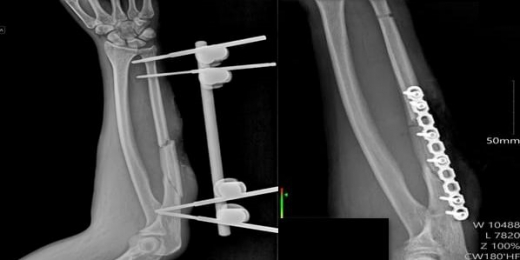

Воронежские медики восстановили пациенту локтевую кость после перелома. Сложный случай лечения тяжелой травмы предплечья успешно завершился в Воронежской городской клинической больнице №2 им. К.В. Федяевского, сообщила пресс-служба облздрава во вторник, 14 октября. Пострадавший поступил в медучреждение с переломом локтевой кости и большой поверхностной раной. Лечение проводили в три этапа. Сначала хирурги провели первичную обработку и установили аппарат внешней фиксации, чтобы стабилизировать сломанную кость. Спустя две недели медики приступили к восстановлению кожного покрова. Для этого была применена аутодермопластика — пересадка расщепленного кожного лоскута, взятого у самого пациента. Тонкий слой кожи с помощью специального инструмента перенесли на рану, предварительно перфорировав для увеличения площади. На заключительном этапе, через три недели, травматологи-ортопеды выполнили открытую репозицию отломков кости и провели погружной остеосинтез — зафиксировали перелом пластиной и винтами. Врачам удалось полностью восстановить анатомию и функции руки. Пациента уже выписали из стационара в удовлетворительном состоянии. Операцию и последующее лечение проводила бригада медиков в составе заведующей хирургическим отделением Светланы Бакулиной, хирурга Любови Семеновой, травматолога-ортопеда Дмитрия Разумного, анестезиолога-реаниматолога Игоря Федорищева, операционной сестры Анны Прокофьевой и медсестры-анестезиста Аллы Беленовой.